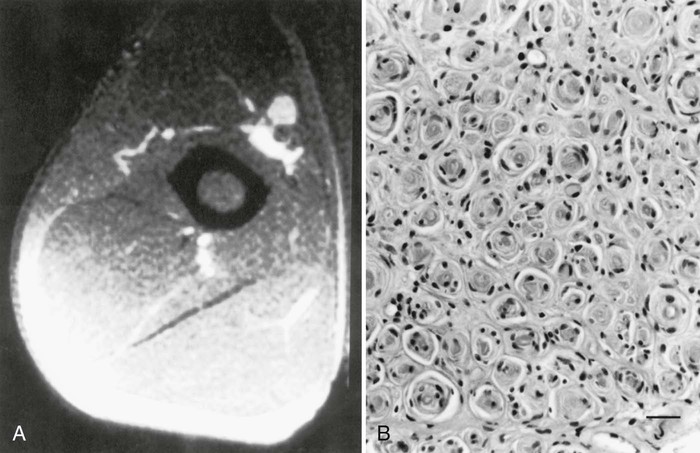

The term segmental demyelination (or myelinopathy) implies injury of either myelin sheaths or Schwann cells, resulting in breakdown of myelin with sparing of axons (Fig. 107.3). This occurs mechanically by acute nerve compression or chronic nerve entrapment and in immune-mediated demyelinating neuropathies and hereditary disorders of Schwann cell/myelin metabolism. Primary myelin damage may be produced experimentally by myelinotoxic agents such as diphtheria toxin or by acute nerve compression. Remyelination of demyelinated segments usually occurs within weeks. The newly formed remyelinated segments have thinner-than-normal myelin sheaths and internodes of shortened length. Repeated episodes of demyelination and remyelination produce proliferation of multiple layers of Schwann cells around the axon, termed an onion bulb. The physiological consequence of acquired demyelination, such as in inflammatory or compressive demyelination but not hereditary myelinopathies, is conduction block, which results in loss of the ability of the nerve action potential to reach the muscle, thereby producing weakness. Because the axon remains intact, there is little muscle atrophy. Relative sparing of temperature and pinprick sensation in many demyelinating polyneuropathies reflects preserved function of unmyelinated and small-diameter myelinated fibers. Early generalized loss of reflexes, disproportionately mild muscle atrophy in the presence of proximal and distal weakness, neuropathic tremor, and palpably enlarged nerves are all clinical clues that suggest demyelinating polyneuropathy. Nerve conduction studies or analysis of single teased nerve fiber preparations stained with osmium can confirm demyelination. Demyelination is present if motor and sensory nerve conduction velocities (NCVs) are reduced to less than 70% of the lower limits of normal, with relative preservation of CMAP and SNAP amplitudes. The presence of partial motor conduction block, temporal dispersion of CMAPs, and marked prolongation of distal motor and F-wave latencies are all features consistent with acquired demyelination (see Chapter 35). Recovery depends on the extent of remyelination, and therefore clinical improvement may occur within weeks. In many demyelinating neuropathies, axonal degeneration may also coexist, as evidenced by some distal limb atrophy and active deneravtion and reinnervation changes on needle EMG.